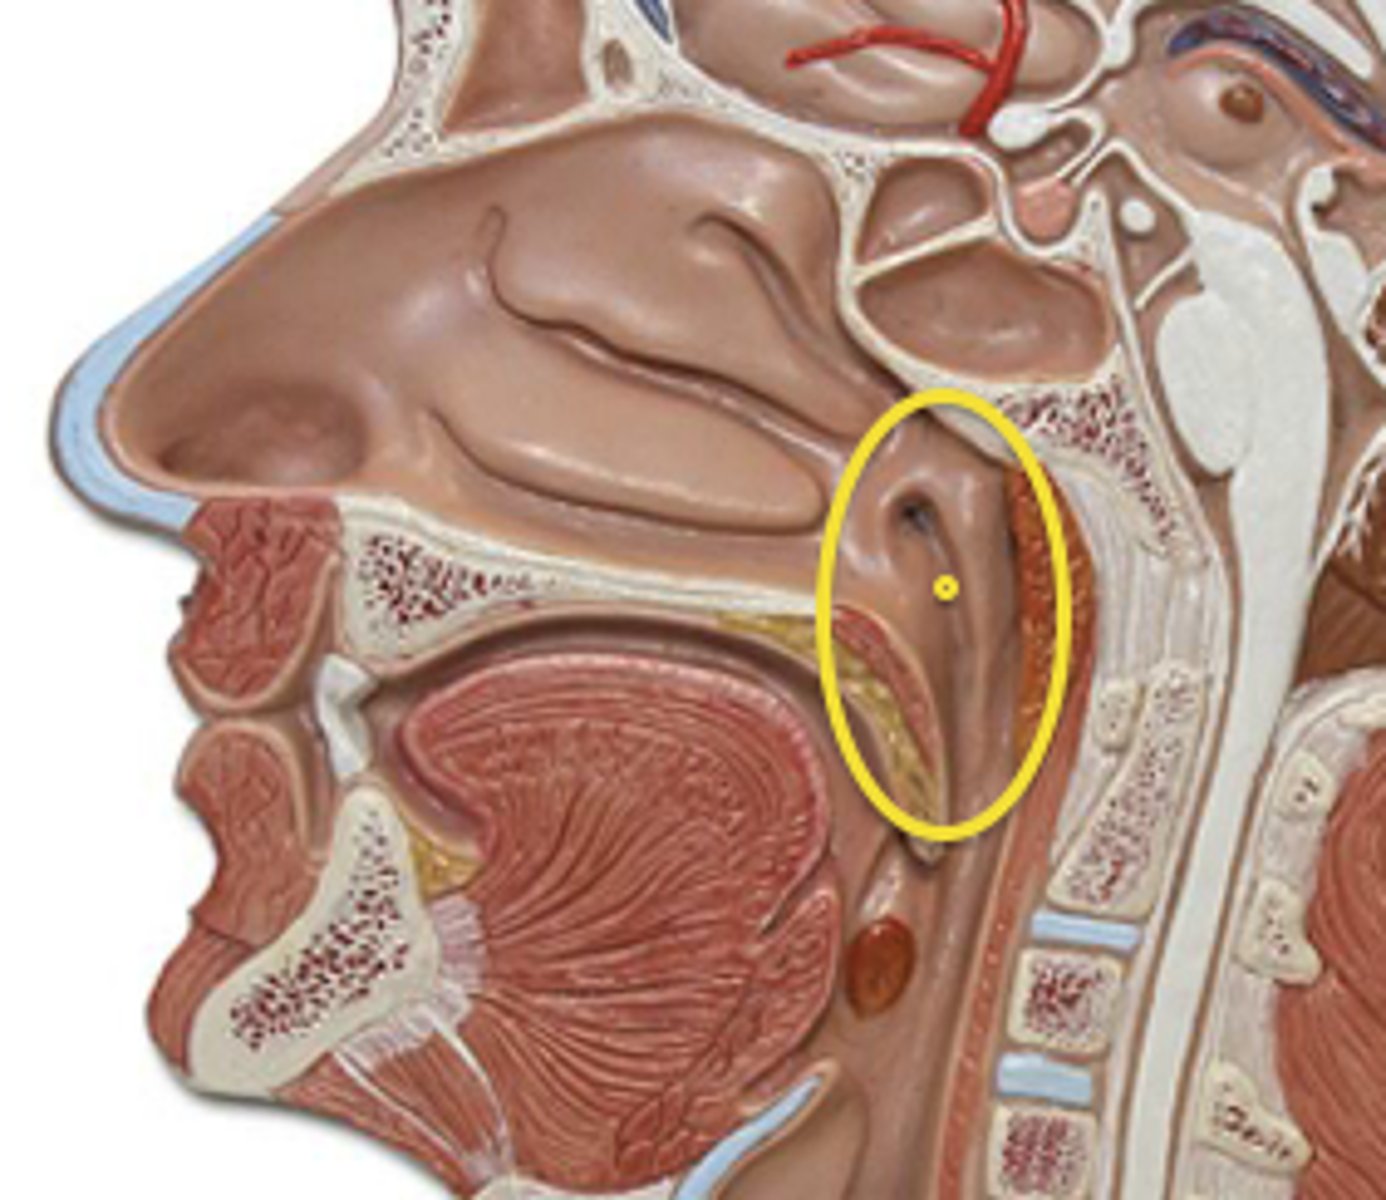

Pharynx

The membrane-lined cavity behind the nose and mouth, connecting them to the esophagus.

Nasopharynx

Region of the pharynx at the back of the nose and above the soft palate

Pharyngeal Orifice of Pharyngotympanic Tube

The base of the cartilaginous portion of the auditory tube

Oropharynx

Central portion of the pharynx between the roof of the mouth and the upper edge of the epiglottis

Laryngopharynx

Lower part of the pharynx, just below the oropharyngeal opening into the larynx and esophagus

Larynx

Voice box; passageway for air moving from pharynx to trachea; contains vocal cords

Epiglottis

A flap of cartilage at the root of the tongue, which is depressed during swallowing to cover the opening of the windpipe